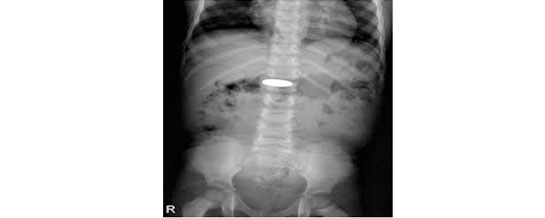

ووفقا لإدارة المدينة الطبية، فقد وصلت الطفلة إلى صالة الطوارئ وهي في حالة حرجة، تعاني من ضيق شديد في التنفس وسعال متواصل، ما استدعى تدخلاً طبياً عاجلاً، حيث أظهرت الفحوصات وجود جسم غريب عالق في المجرى التنفسي العلوي.

-الصورة من الارشيف